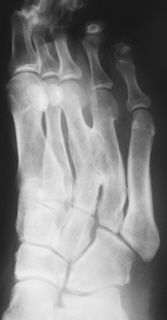

Иллюстрация 2. Рентгенограмма в косой проекции. Визуализируется деформация 3 и 4 плюсневых костей, синостоз между диафизами 3 и 4 плюсневых костей.